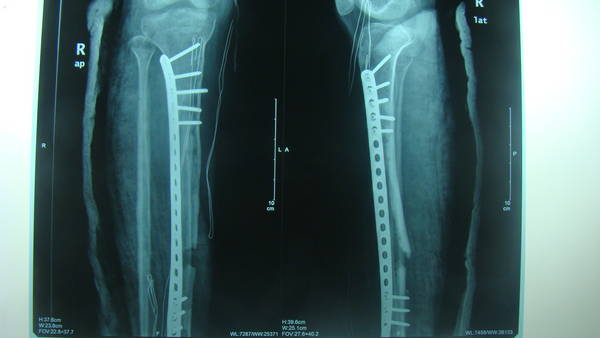

[修复重建] 游离腓骨移植术

广西玉林红十字会医院,用颈前动脉跟腓动脉吻合。血供肯定没问题。吻好后腓骨断端出血好,回流静脉充盈。

“厉害。请问楼主血管吻合口正在钢板上方。会不会因为钢板刺激加重血管痉挛?希望能看看术后X线片。”

这个问题我考虑了,官主任说过血管床很重要,所以在吻合前专门盖了一块软组织。防止钢板电解影响血管

补发术前术后照片